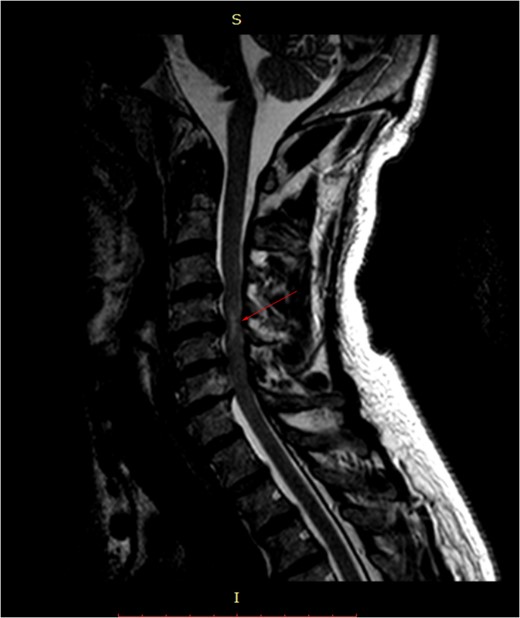

Pre-surgery sagittal MRI. Arrowhead points towards a focus of T2-hyperintensity at the C5-C6 level.

MRI is the study of choice. Some researchers advocate the use of a low focal T1 and/or high T2 signal as a negative prognostic factor regarding post-treatment outcome, while others defy it.